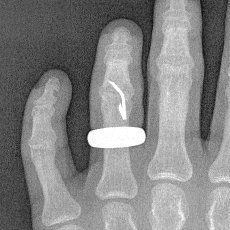

That’s what I’m doing today thanks to a relatively freak accident with a staple gun yesterday. I won’t bore you with the details (that would confirm what a bonehead I can be sometimes). Just suffice it to say that, it could have been a lot worse.